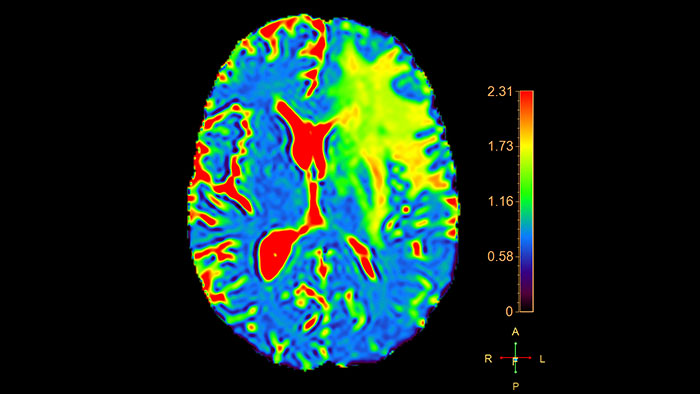

MR T2* (Neuro) Perfusion

Reviewing brain tissue perfusion viability

Provides physicians with supporting information for the evaluation of stroke, or assessment and follow-up of brain tumors. The application supports the analysis of T2* Perfusion studies to generate parametric data including TTP, MTT or Tmax.

Benefits

• Offers several analysis techniques such as leakage correction, which allows to assess the time intensity curves where there is no proper recovery of the baseline after contrast passage, and manual arterial input function (AIF) which enables perfusion-diffusion mismatch if a Diffusion input dataset is available in addition to the Perfusion series.

• The package includes user-selected color coding of the functional data, and maps can be viewed and stored as overlays on anatomical reference images.